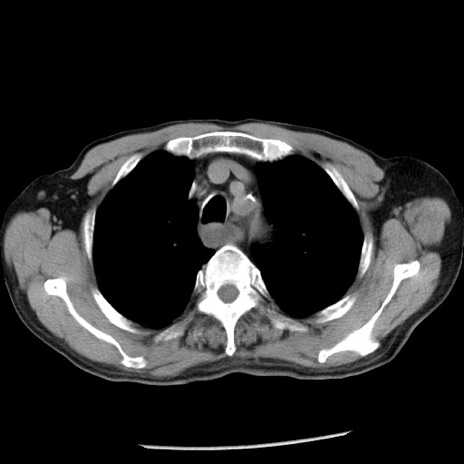

症例26(横断像)

【症例】80歳代男性

【主訴】嘔吐

【現病歴】昨晩2回嘔吐あり、今朝になっても嘔吐あり。来院。

【既往歴】胃潰瘍

【身体所見】意識清明、BT 37.6℃、BP 166/95mmHg、HR 100bpm、SpO2 97%、腹部:平坦・軟、腸蠕動音聴取良好、圧痛なし。

【データ】WBC 21900、CRP 1.46